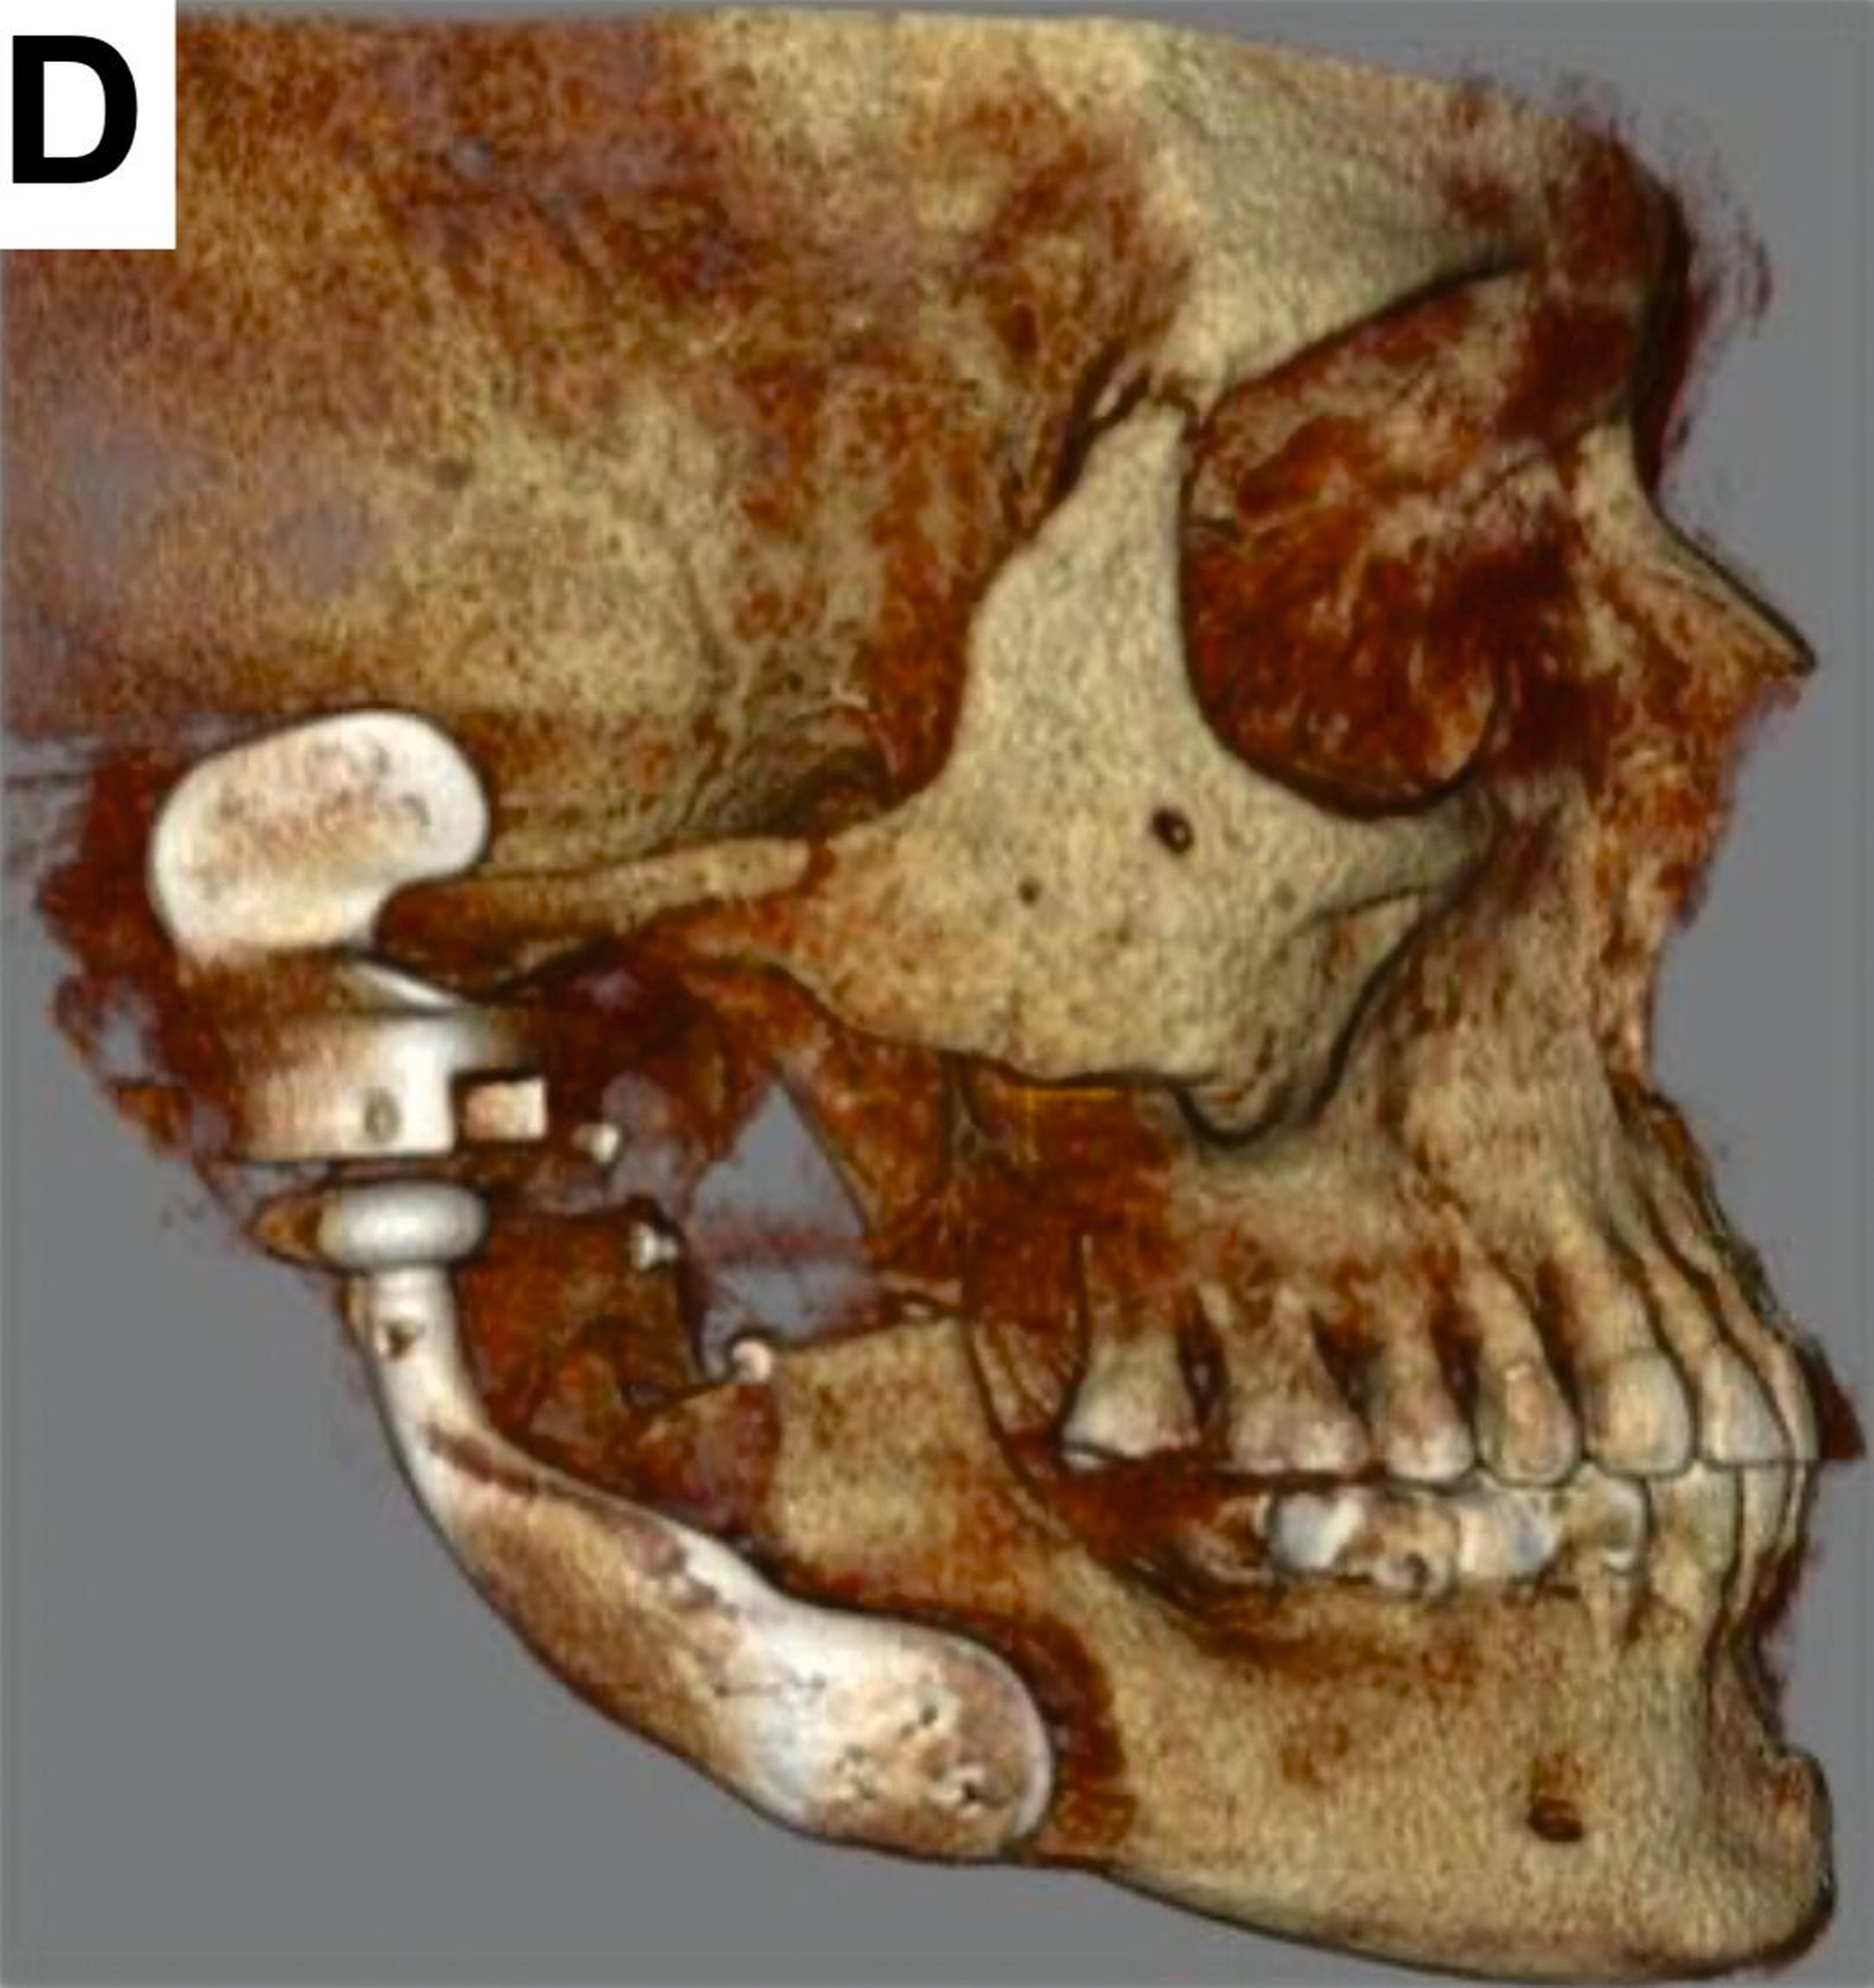

Nach einer achtmonatigen Konsolidierungsphase unter Verwendung einer Okklusionsschiene wurde zur Planung einer industriell gefertigten CAD/CAM-Kiefergelenk-Totalendoprothese ein Dünnschicht-CT durchgeführt (Abbildung 3).